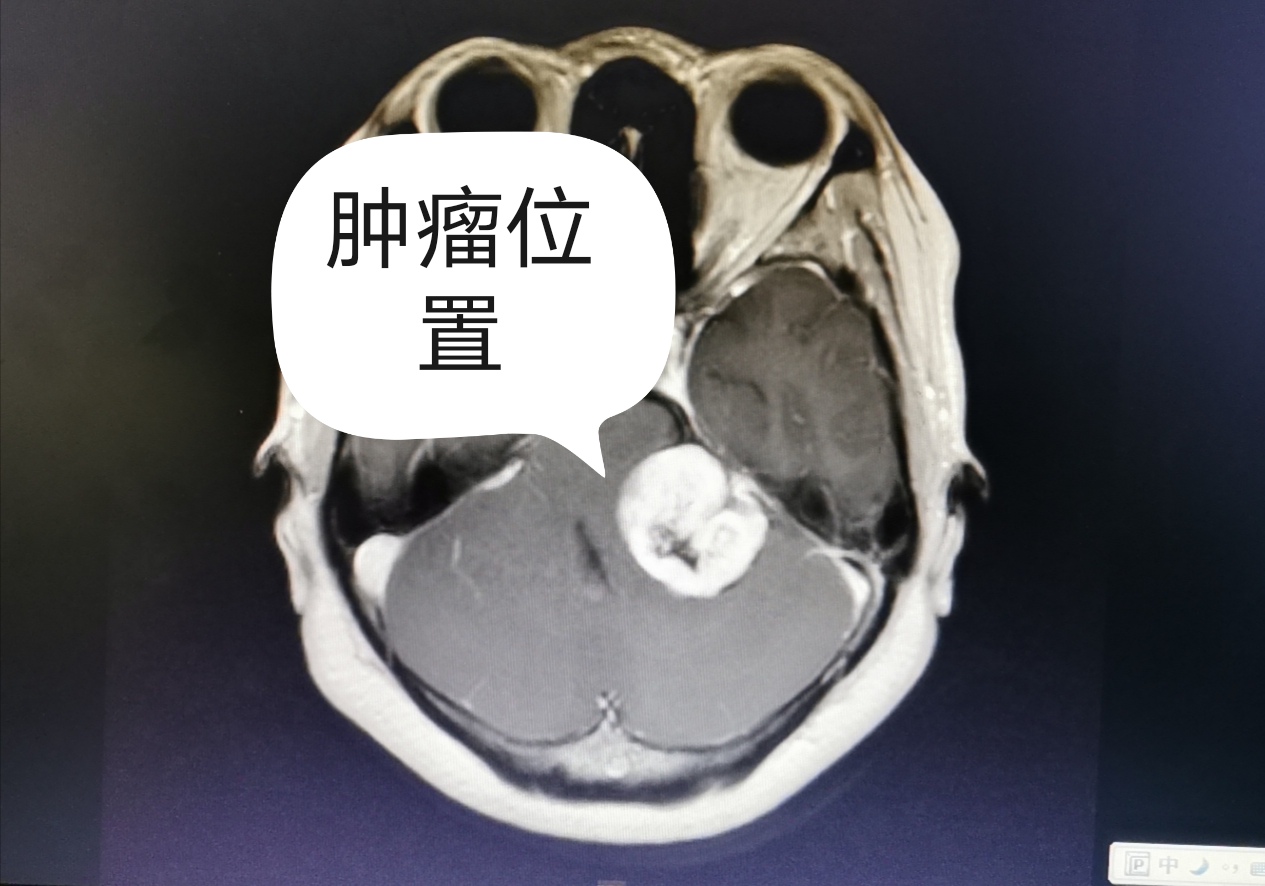

40岁的韦女士因左耳耳鸣伴右侧面部麻木1年余,在家属陪同下来到我院神经外科就诊。行头颅CT及磁共振检查提示左侧桥小脑角区占位,肿瘤位于小脑幕以下,基底部位于内听道,与听神经、面神经、三叉神经紧密相连,血运丰富,大小约为3.5cm×3.0cm×1.6cm。需要尽快手术治疗。术前,神经外科医疗团队根据患者的肿瘤位置、大小,性质和颅神经保护等方面进行全面的评估和讨论,制定出最适合患者的治疗方案,在显微镜下为患者进行肿瘤切除术。术后患者面部麻木症状明显好转,病理诊断提示神经鞘瘤,患者的听力在进一步康复治疗中。

术前头颅CT